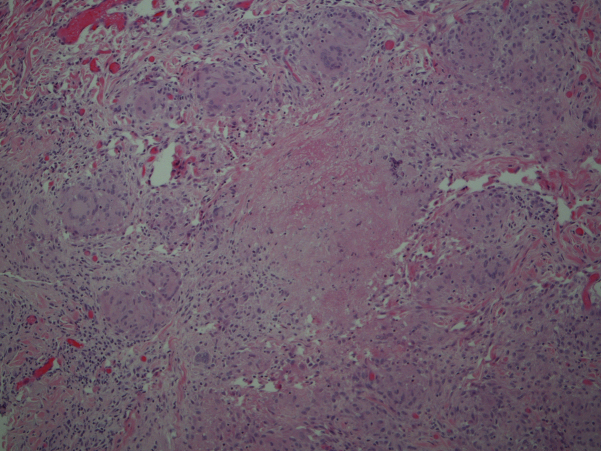

Fig 2.

Histologic examination of a punch biopsy taken from the patient's left axilla shows aggregates of palisading epithelioid cells, caseation necrosis, and multinucleated giant cells. (Hematoxylin-eosin stain; original magnification: ×10.)

Histopathologic analysis found dermal aggregates of palisading epithelioid cells with occasional neutrophils and fibrin deposition. Multinucleated giant cells were noted and occasionally exhibited phagocytosis of elastic fibers. Focal necrosis occurred in some of the granulomas. Staining for fungi and acid-fast bacilli was negative.